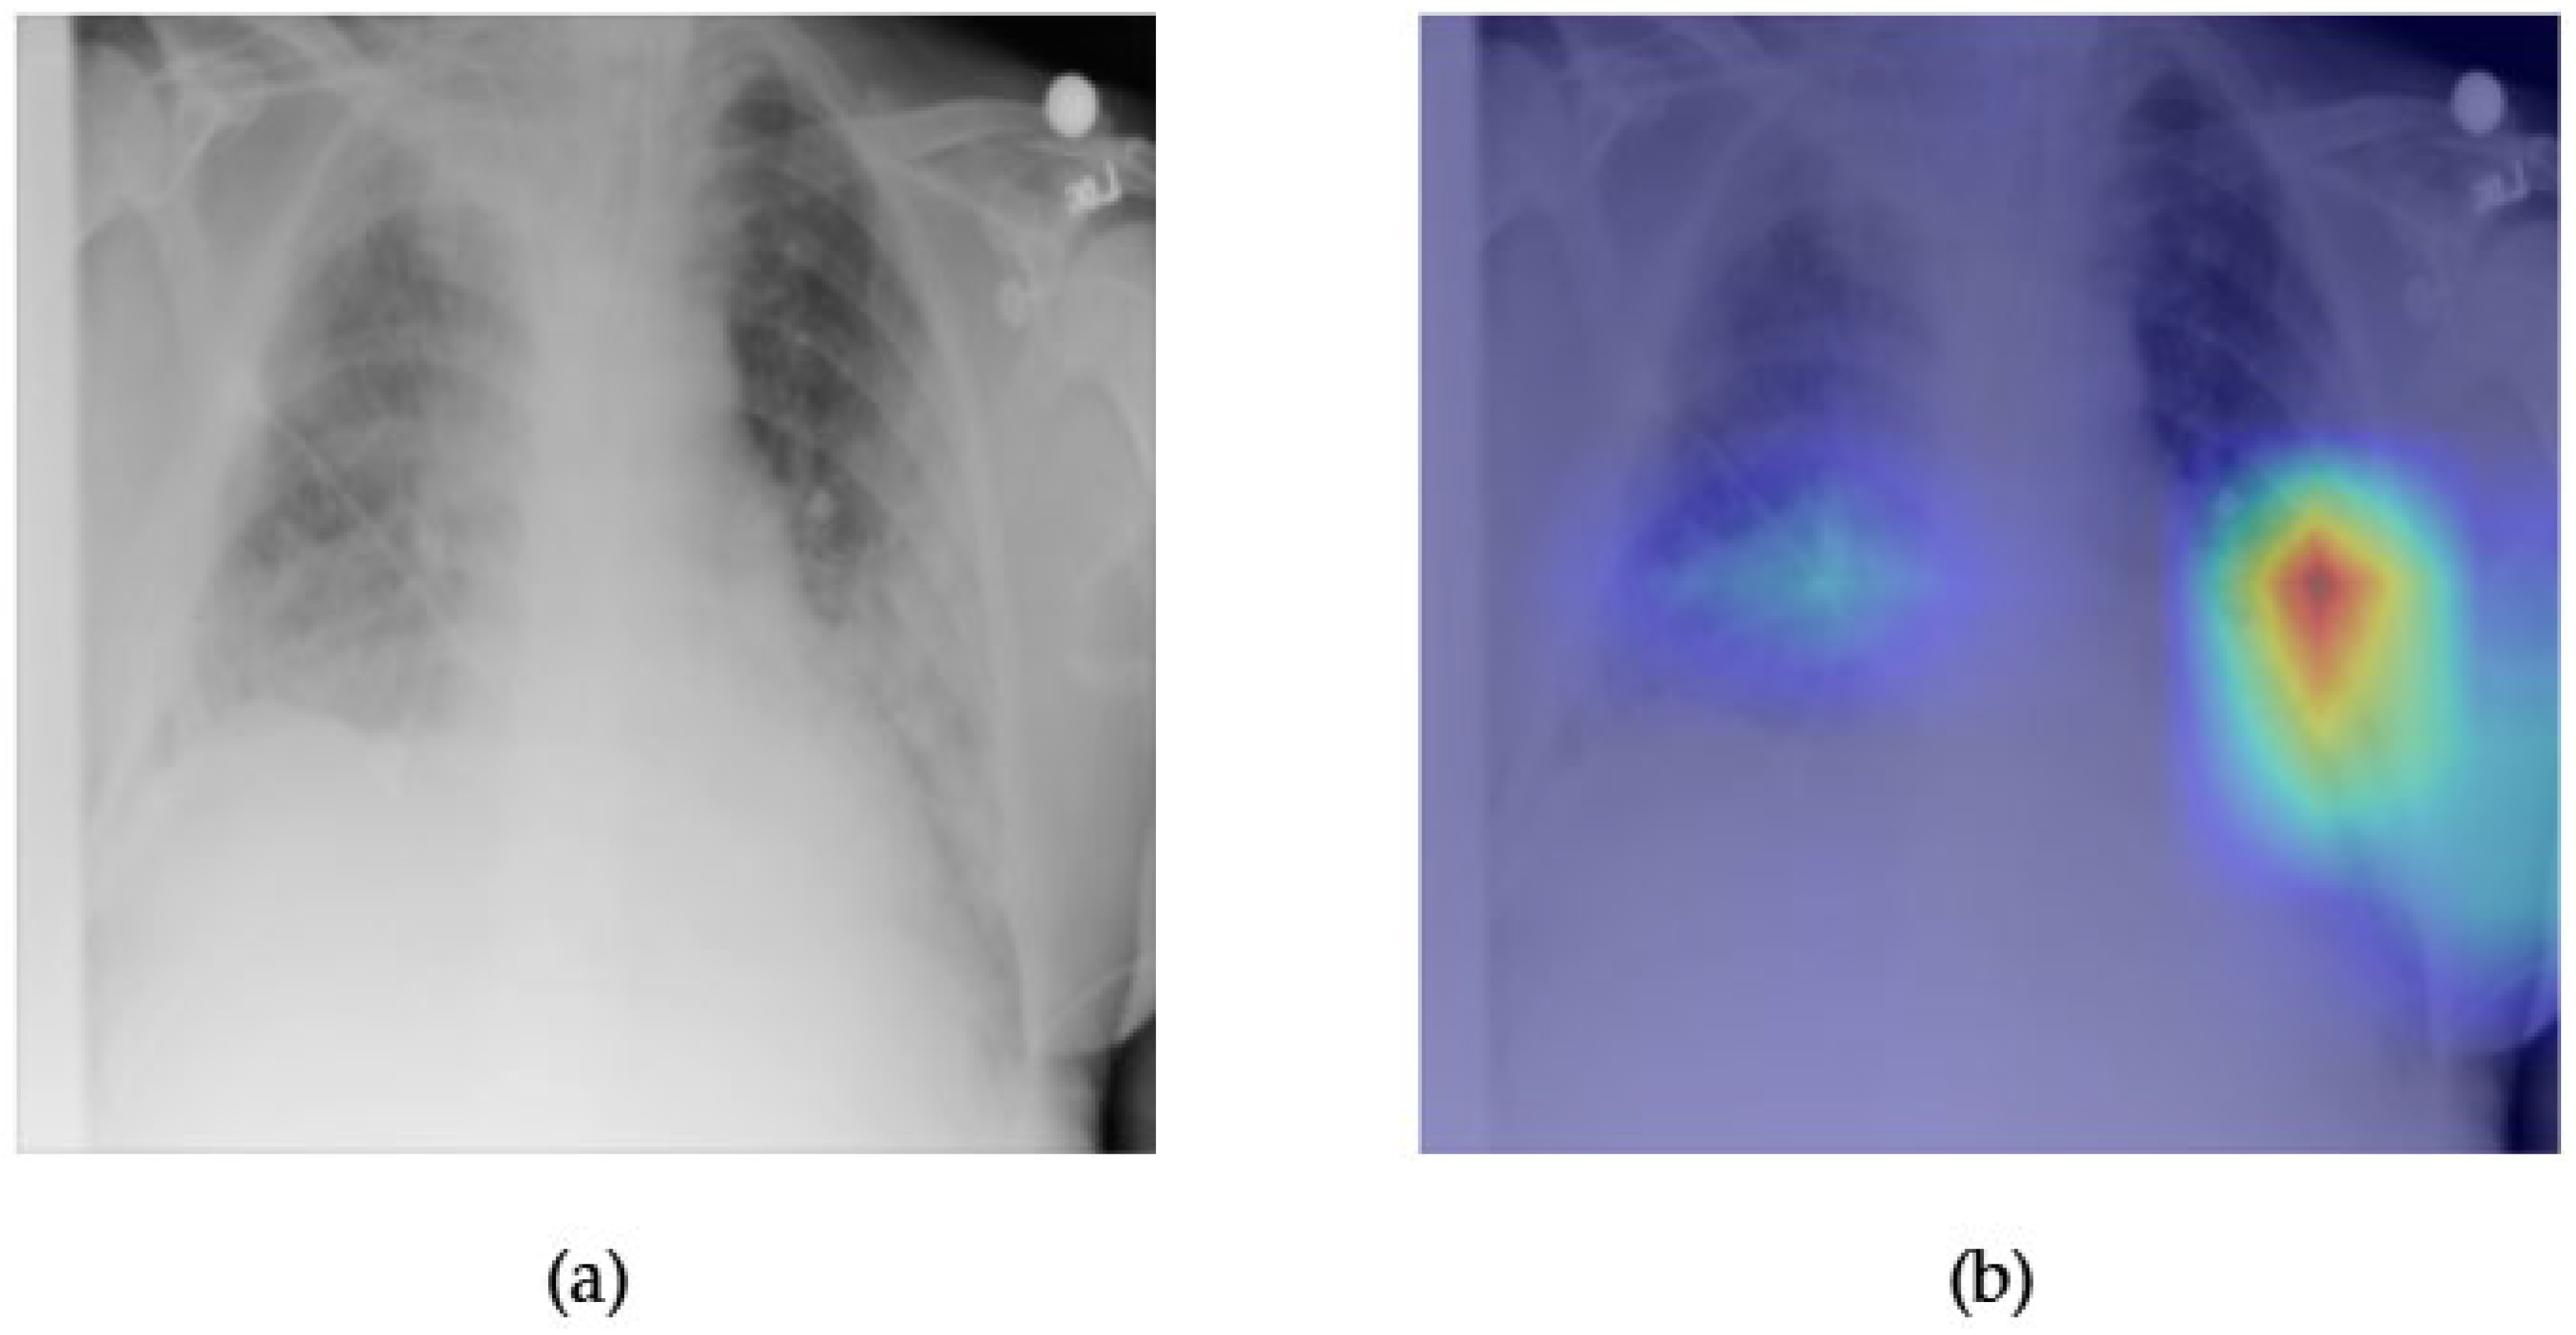

- Although our Grad-CAM-based explainability provides useful localization cues, it is inherently limited by its post hoc nature and reliance on gradient flow from the final convolutional layers. Future research could incorporate advanced interpretability techniques such as Layer-wise Relevance Propagation (LRP), Integrated Gradients, or attention rollouts in Transformers, which may offer a more complete understanding of model reasoning.